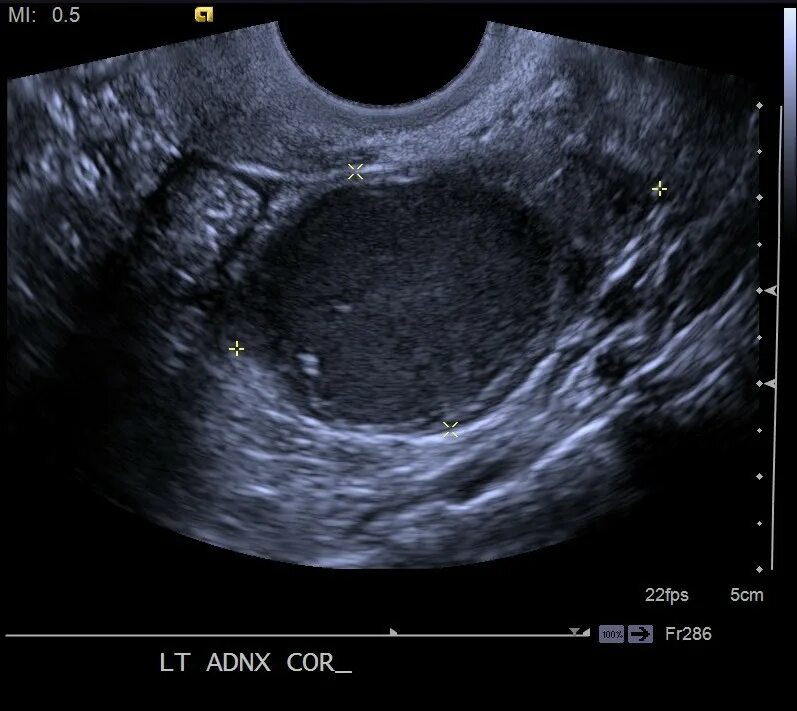

Как выглядит яичник